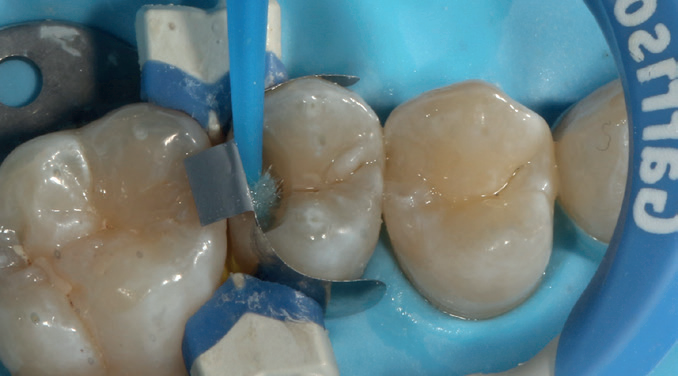

After removing the decay, I took several photos to help illustrate the cavity’s extent. I then placed a sectional matrix to ensure proper contact closure, as the cavity was large. After this, I applied Stela.

Figure 5: Teeth have been conditioned using air abrasion

Figure 6: Sectional matrix placement followed by placement of the Stela primer for five seconds